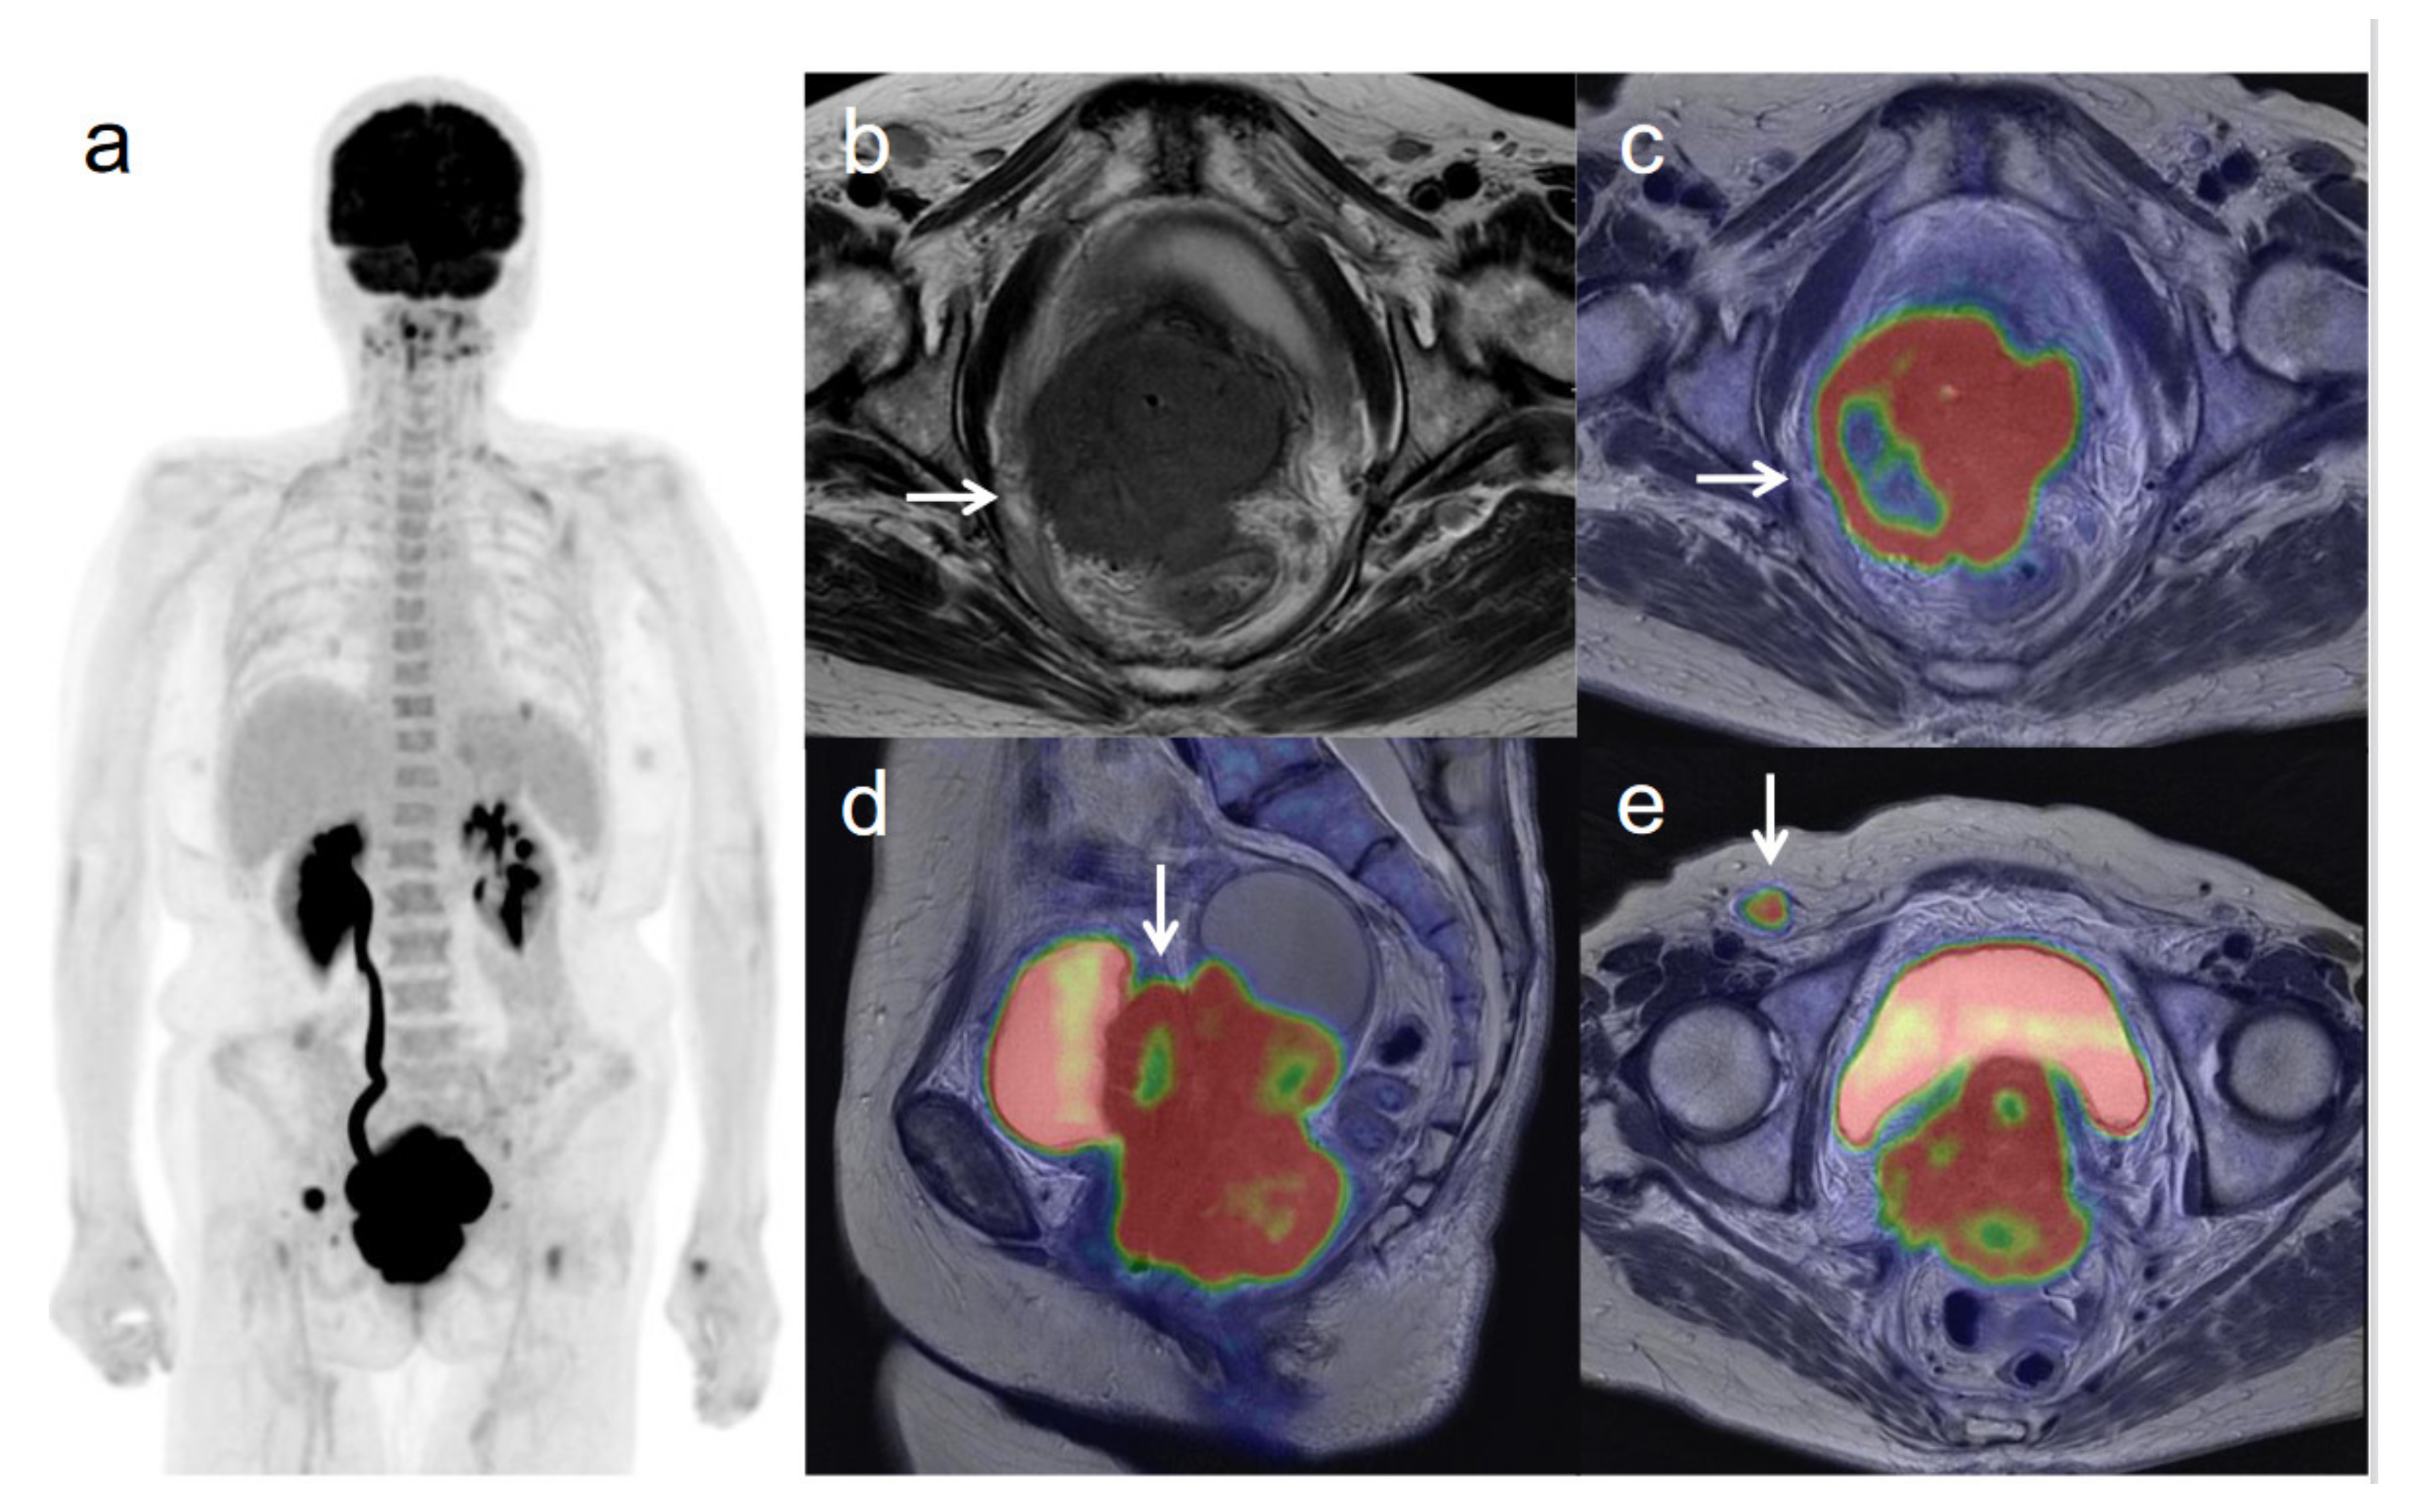

3.3. Revised FIGO Staging

Figure 1. A 54-year-old woman with stage IIIC1 cervical cancer with parametrial invasion. (a) 18F-FDG PET image shows FDG uptake by tumor in the cervical cervix (arrow) and pelvic lymph nodes. (b) Axial T2-weighted pelvic MR image shows parametrial invasion with disruption of the right cervical stroma by the tumor but no extension into the pelvic side wall (arrow). (c) Axial T2-weighted PET/MR image shows FDG uptake by the tumor, which invades the right parametrium with disruption of the cervical stroma, but no extension into the pelvic side wall (arrow). These appearances are consistent with the clinical findings. (d) Sagittal T2-weighted PET/MR image shows FDG uptake by the cervical tumor. (e) Coronal T2-weighted PET/MR image shows FDG uptake by the cervical tumor and pelvic lymph nodes (arrows).